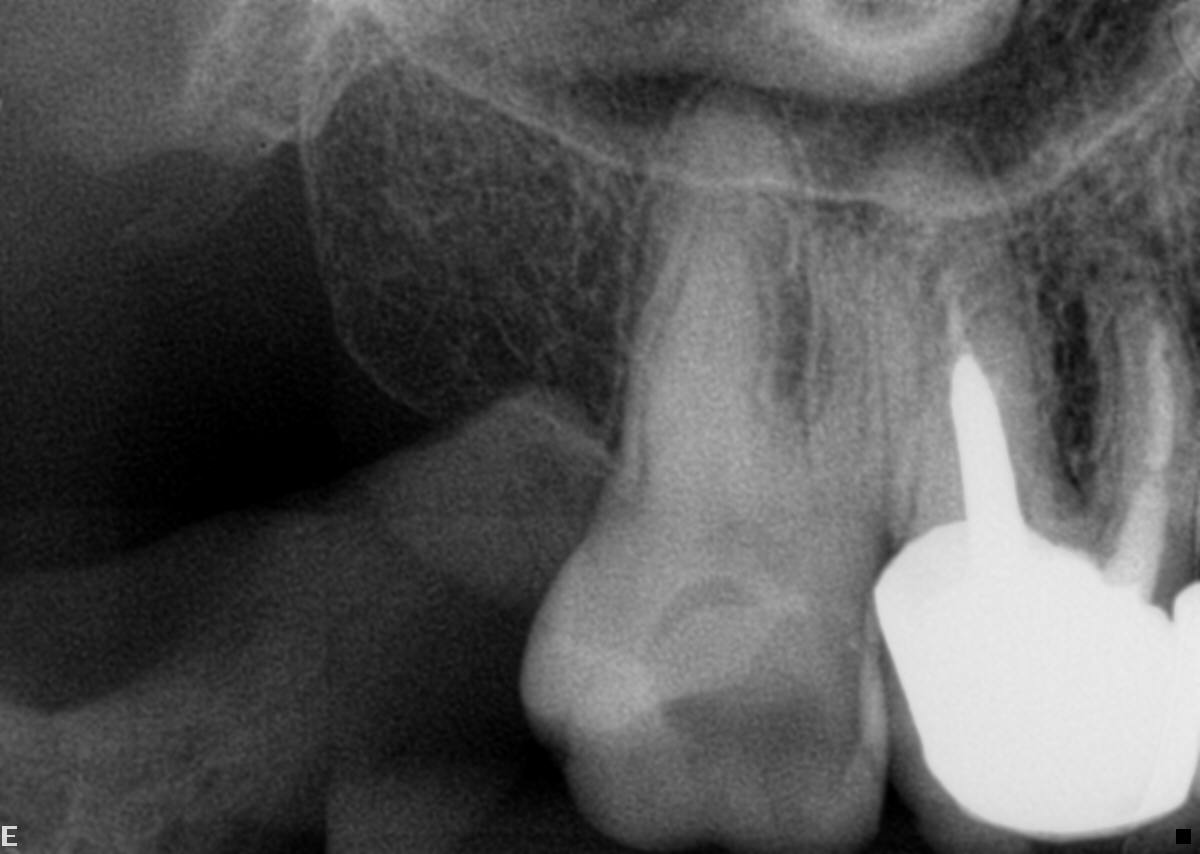

- Paciente do sexo feminino, com 70 anos de idade, nos procurou com queixa de dor no dente 17 (Figura 2).

- Em seguida, relatou ter passado por um profissional que solicitou a ajuda de microscópio por não conseguir descer nos canais. Então, fizemos uma radiografia periapical onde constatou-se atresia em raiz distal, e atresia e curvatura em raiz mesial (Figura 3).

Figura 2 Figura 3 Figura 4 Figura 5 Figura 6 Figura 7